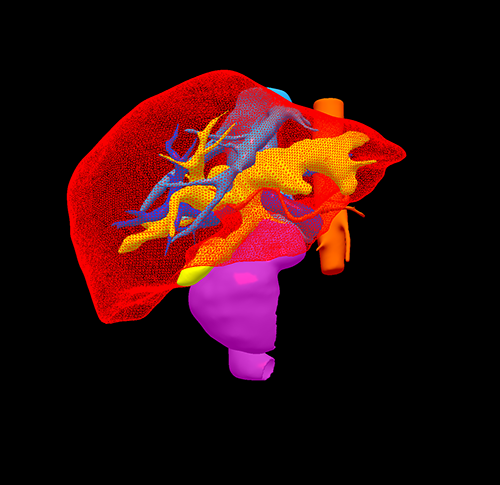

右肝内胆管结石、 胆管十二指肠瘘--S67肝切除、胆肠吻合、十二指肠瘘修补